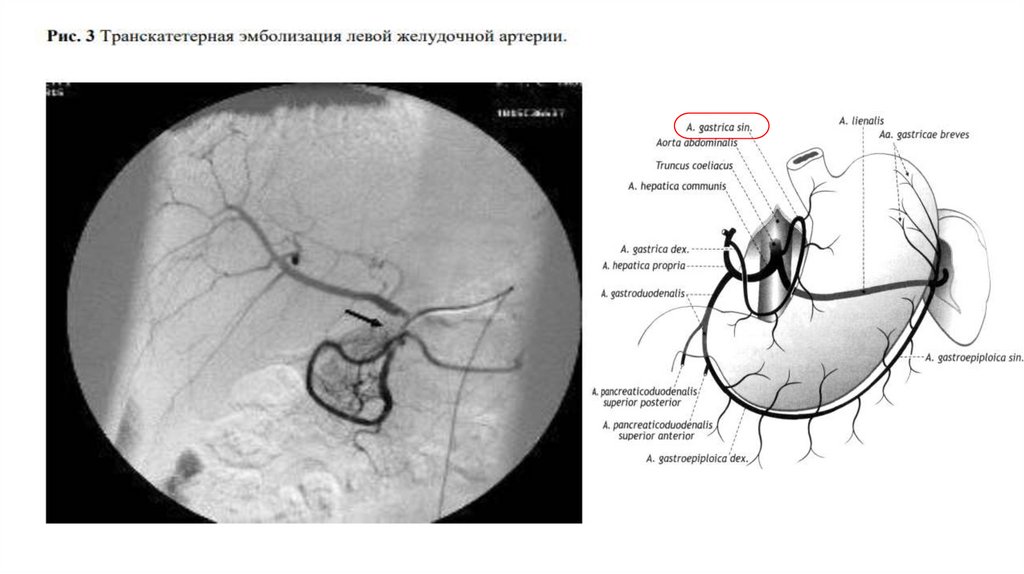

Эндоваскулярное лечение

Рекомендуется транскатетерная ангиографическая эмболизация

артерий желудка и двенадцатиперстной кишки, как альтернатива

хирургическому лечению, при неоднократно рецидивирующих ЯГДК

резистентных к эндоскопическому и медикаментозному гемостазу.

Рекомендации о профилактической (до развития рецидива

кровотечения) эмболизации артерий желудка и

двенадцатиперстной кишки у больных высокого риска отсутствуют.

ТАЭ

Транскатетерную артериальную эмболизацию выполняется из бедренного

доступа. Последовательно производится селективная ангиографию

селезеночной, левой желудочной, желудочнодвенадцатиперстной артерии и

ее ветвей и ветвей верхней брыжеечной артерий с целью определения прямых

и косвенных ангиографических признаков кровотечения. К прямым признакам

относятся экстравазацию контрастированной крови, к косвенным тромботическую окклюзию сосудов, регионарный артериальный спазм,

аневризмы ветвей чревного ствола, а также признаки локальной

гиперваскуляризации и периартериальной диффузии контрастированной

крови. Далее выполняется локальную или сегментарную эмболизацию участка

или всего сосуда, являющегося источником кровотечения. В качестве эмбола

используется адгезивного клеевый композит разведенный с

рентгеноконтрастным веществом. Успехом ТАЭ считается отсутствие кровотока

в эмболизируемой артерии. После эмболизации для исключения кровотечения

из коллатеральных ветвей необходима контрольная ангиограмма чревного

ствола и верхней брыжеечной артерии.